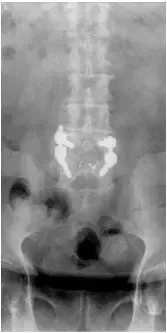

X-rays and MRI of the Lumbar spine showed L4-5 degenerative spondylolisthesis

and severe spinal stenosis.

Patient underwent decompression laminectomy with decompression of nerve roots and transforaminal interbody fusion using PEEK (polyether ether ketone) cage and pedicle screw and rod fixation for fusion at L4-5 level.